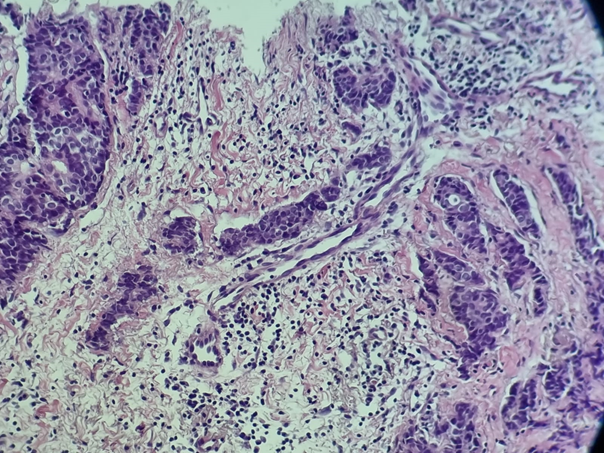

As part of the etiological diagnosis, the patient was referred to our medical oncology department at the Mohamed VI University Hospital. Our clinical examination found a two-centimeter nodule in the left breast that was mobile in relation to the two planes, and the echomammography showed a multifocal multicentric left breast with 5 nodules classified as Birads 5. The extension evaluation was mainly based on a thoracic-abdominal-pelvic scanner which did not reveal the presence of metastases. The histological diagnosis revealed the presence of a poorly differentiated infiltrating breast carcinoma (Figure 1), grade III SBR, with hormone receptors-positif , human epidermal growth factor receptor 2-negative (HR+/HER2−) and the Ki 67 is 30%.

Figure 1 Histological image showing a poorly differentiated infiltrating breast carcinoma.